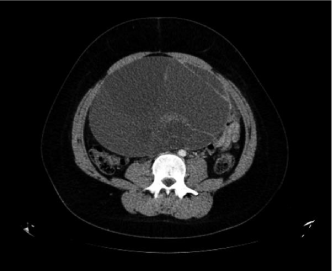

A 16-year-old previously healthy female presented to the emergency department in 2016 with a three-month history of amenorrhea and intermittent abdominal discomfort. Examination revealed a pelvic mass extending up to the xiphoid process, confirmed on CT to be a multiseptated cyst with solid and cystic components, associated with right hydroureteronephrosis (Figure 1a). A raised CA 19.9 level of 76.1 U/mL (0-33 U/mL) was noted, although other markers were normal. The patient was scheduled for urgent outpatient follow-up however re-presented three days later with severe abdominal pain. Emergency laparotomy showed an irregular left ovarian cyst, the posterior aspect of which was disrupted, together with approximately 2 L of blood-tinged fluid in the peritoneal cavity. The mass had a multicystic cut surface, with the subcysts containing serosanguinous fluid and solid areas. Histology showed a juvenile-type GCT with a mitotic index of 17 MF/10 HPF (Figure 1b). Right ovarian biopsies and omental biopsies were also taken but did not show evidence of tumour. Surveillance has, till now, been unremarkable with normal Inhibin B levels and MR imaging (Figure S1).

Figure S1: Axial CT image showing a multiseptated adnexal cyst with solid and cystic components as described in Case 2. View Figure S1